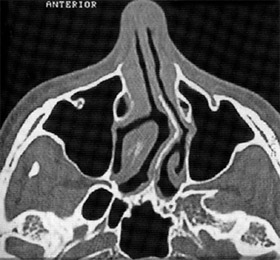

Αξονική τομογραφία: Εμφανής η σκολίωση του ρινικού διαφράγματος.

Εμφανής η σκολίωση του ρινικού διαφράγματος.